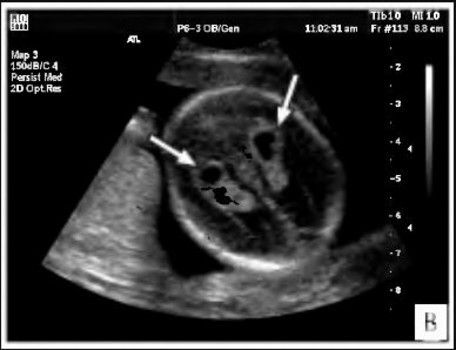

Сосудистые сплетения у плода образуются на сроке 18-19 недель. Именно в этот период, при проведении УЗИ могут быть обнаружены первые признаки кист, которые выглядят, как эхонегативные образования. Чаще всего в срок от 20 до 24 недель, когда идет активное формирование головного мозга, размер кисты уменьшается, и она полностью исчезает.

Образование подобного полостного сплетения, расположенного в правом желудочке мозга, является односторонним. Если у ребенка есть генетические отклонения в структуре мозга, там возможны аномальные изменения. Их легко увидеть во время ультразвукового исследования.При расположении кисты в боковом сплетении наблюдается пониженное ХГЧ, что указывает на врожденную аномальную патологию.

Встречаются также билатеральные кистозные образования сплетений сосудов в мозговых тканях, которые являются двусторонними поражениями. Структура тканей и сосудов мозга не нарушается, но при этом киста затрагивает сплетения сосудов одного бокового желудочка или обоих.